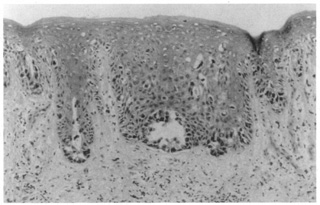

Histologically, the epidermis shows papillomatosis and cystic invaginations into the dermis. Papillary projections lined by two rows of glandular epithelium extend into the lower portion of the cystic spaces (Fig. 39). The luminal row of cells are columnar and may show decapitation secretion, whereas the inner row of cells are small and cuboidal. A characteristic feature of this tumor is a dense plasmacytic infiltrate in the stroma, especially the papillary projections.

Fig. 39. Syringocystadenoma papilliferum. A. Clinical appearance of lesion. B. Numerous cystic spaces in the dermis contain papillary projections. C. Apical (decapitation) secretion from the papillary projection with a dense plasmacytic infiltrate in the stroma.